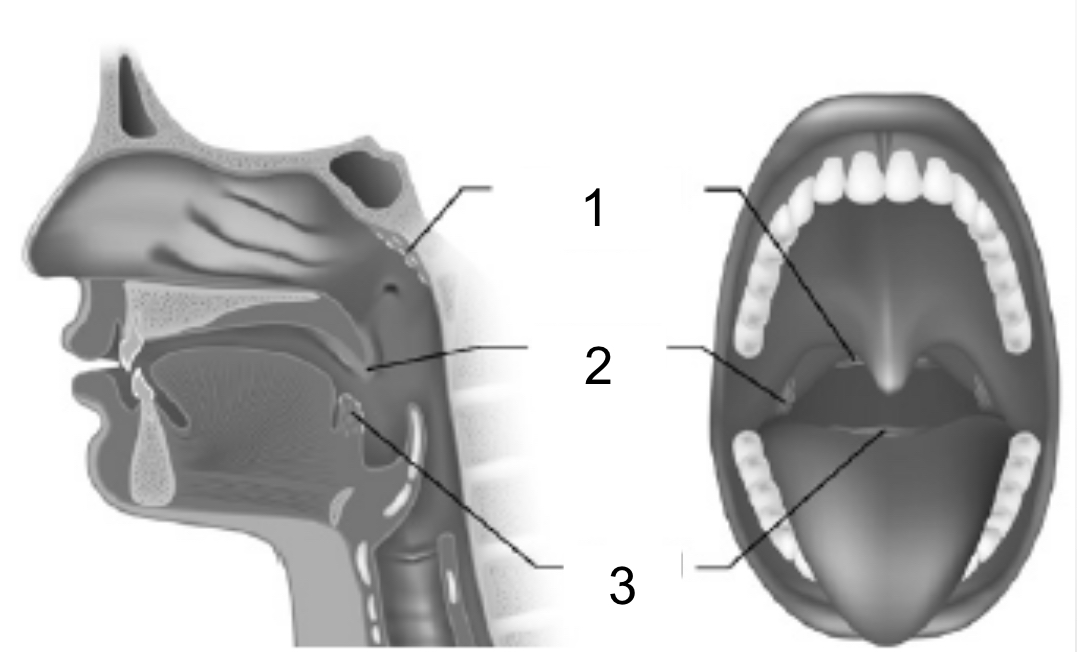

Pharyngeal Tonsil

1

Palatine tonsil

2

Lingual Tonsil

3